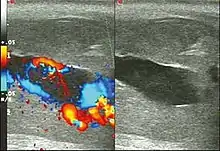

Blood gas testing the blood from the cavernosa of the penis can help in the diagnosis.[3] If the low flow type of priapism is present, the blood typically has a low pH, while if the high flow type is present, the pH is typically normal.[3] Color doppler ultrasound may also help differentiate the two.[3] Testing a person to make sure they do not have a hemoglobinopathy may also be reasonable.[3]

Ultrasonography

Penile ultrasonography with doppler is the imaging method of choice, because it is noninvasive, widely available, and highly sensitive. By means of this method, it is possible to diagnose priapism and differentiate between its low- and high-flow forms.[13]

In low-flow (ischemic) priapism the flow in the cavernous arteries is reduced or absent. As the condition progresses, there is an increase in echogenicity of the corpora cavernosa, attributed to tissue edema. Eventually, changes in the echotexture of the corpora cavernosa can be observed due to the fibrotic transformation generated by tissue anoxia.[13]

In high-flow priapism normal or increased, turbulent blood flow in the cavernous arteries is seen. The area surrounding the fistula presents a hypoechoic, irregular lesion in the cavernous tissue.[13]